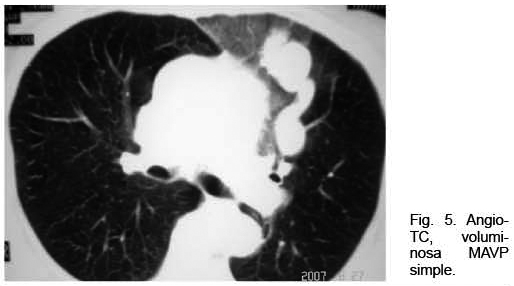

Mujer de 73 años con antecedentes familiares de ROW. Antecedentes personales de AIT un año antes. Ingresó por hemoptisis. Del examen físico se destacaba la presencia de múltiples telangiectasias en piel y mucosas; no presentaba cianosis. La gasometría arterial mostraba una hipoxemia severa. La RxTx mostró una opacidad homogénea polilobulada de 4 centímetros de diámetro mayor, de proyección hiliar izquierda, topografiada a nivel de la língula (Figura 4). Se complementó la valoración con angioTC que confirmó la presencia de múltiples malformaciones arteriovenosas izquierdas pequeñas, junto con una predominante de aproximadamente 5 cm de diámetro de aspecto varicoso, a nivel de língula, con evidencia de sangrado a dicho nivel (Figura 5). Se realizó arteriografía con embolización con “coils” de MAVP predominante con buena evolución.